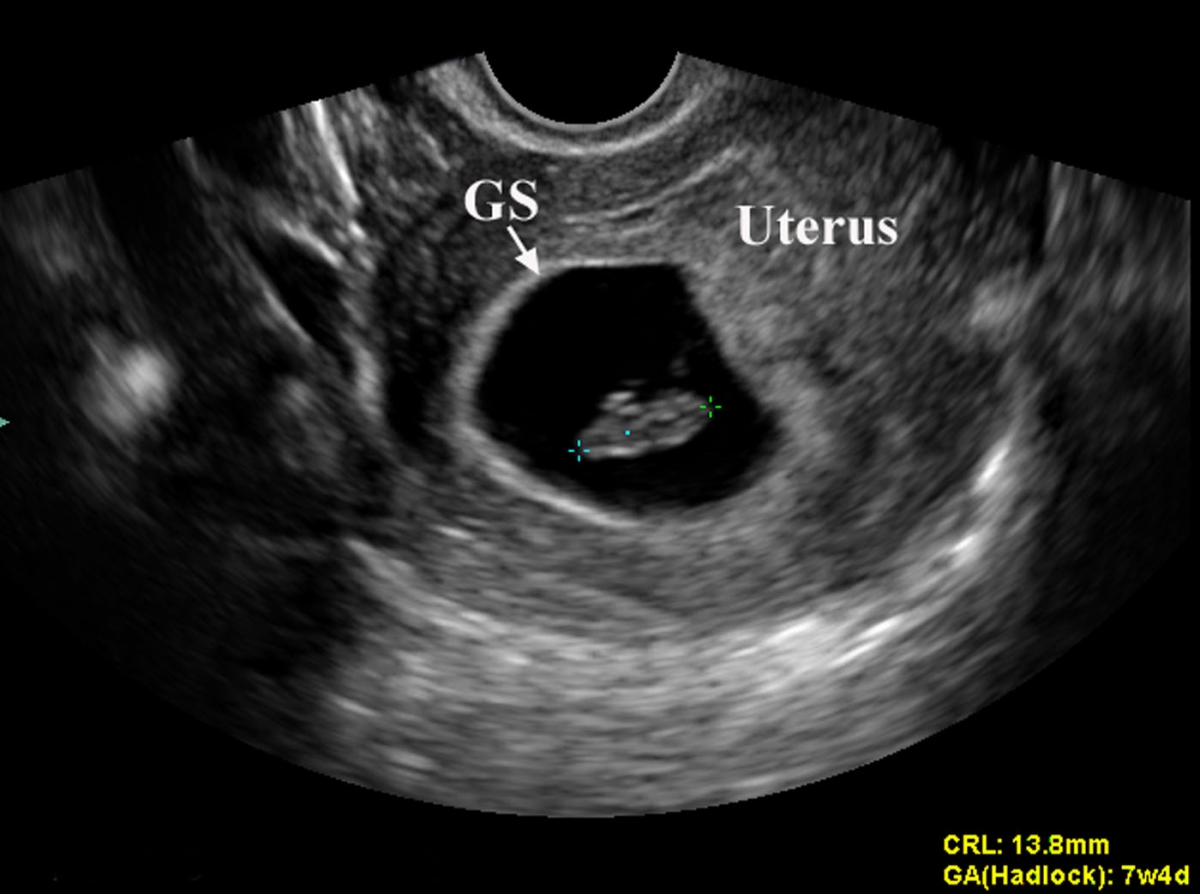

Gestational Sac Measurement Ultrasound How To Calculate Gestational Sac Size The mean sac diameter (msd) calculator is designed to estimate the size of the gestational sac which can be used to help in determining the. How do you calculate the size of the gestational sac? Gestational age = 4 weeks plus (mean sac diameter in mm x days). Mean sac diameter (msd) is a sonographic measurement of the gestational sac,. How To Calculate Gestational Sac Size.